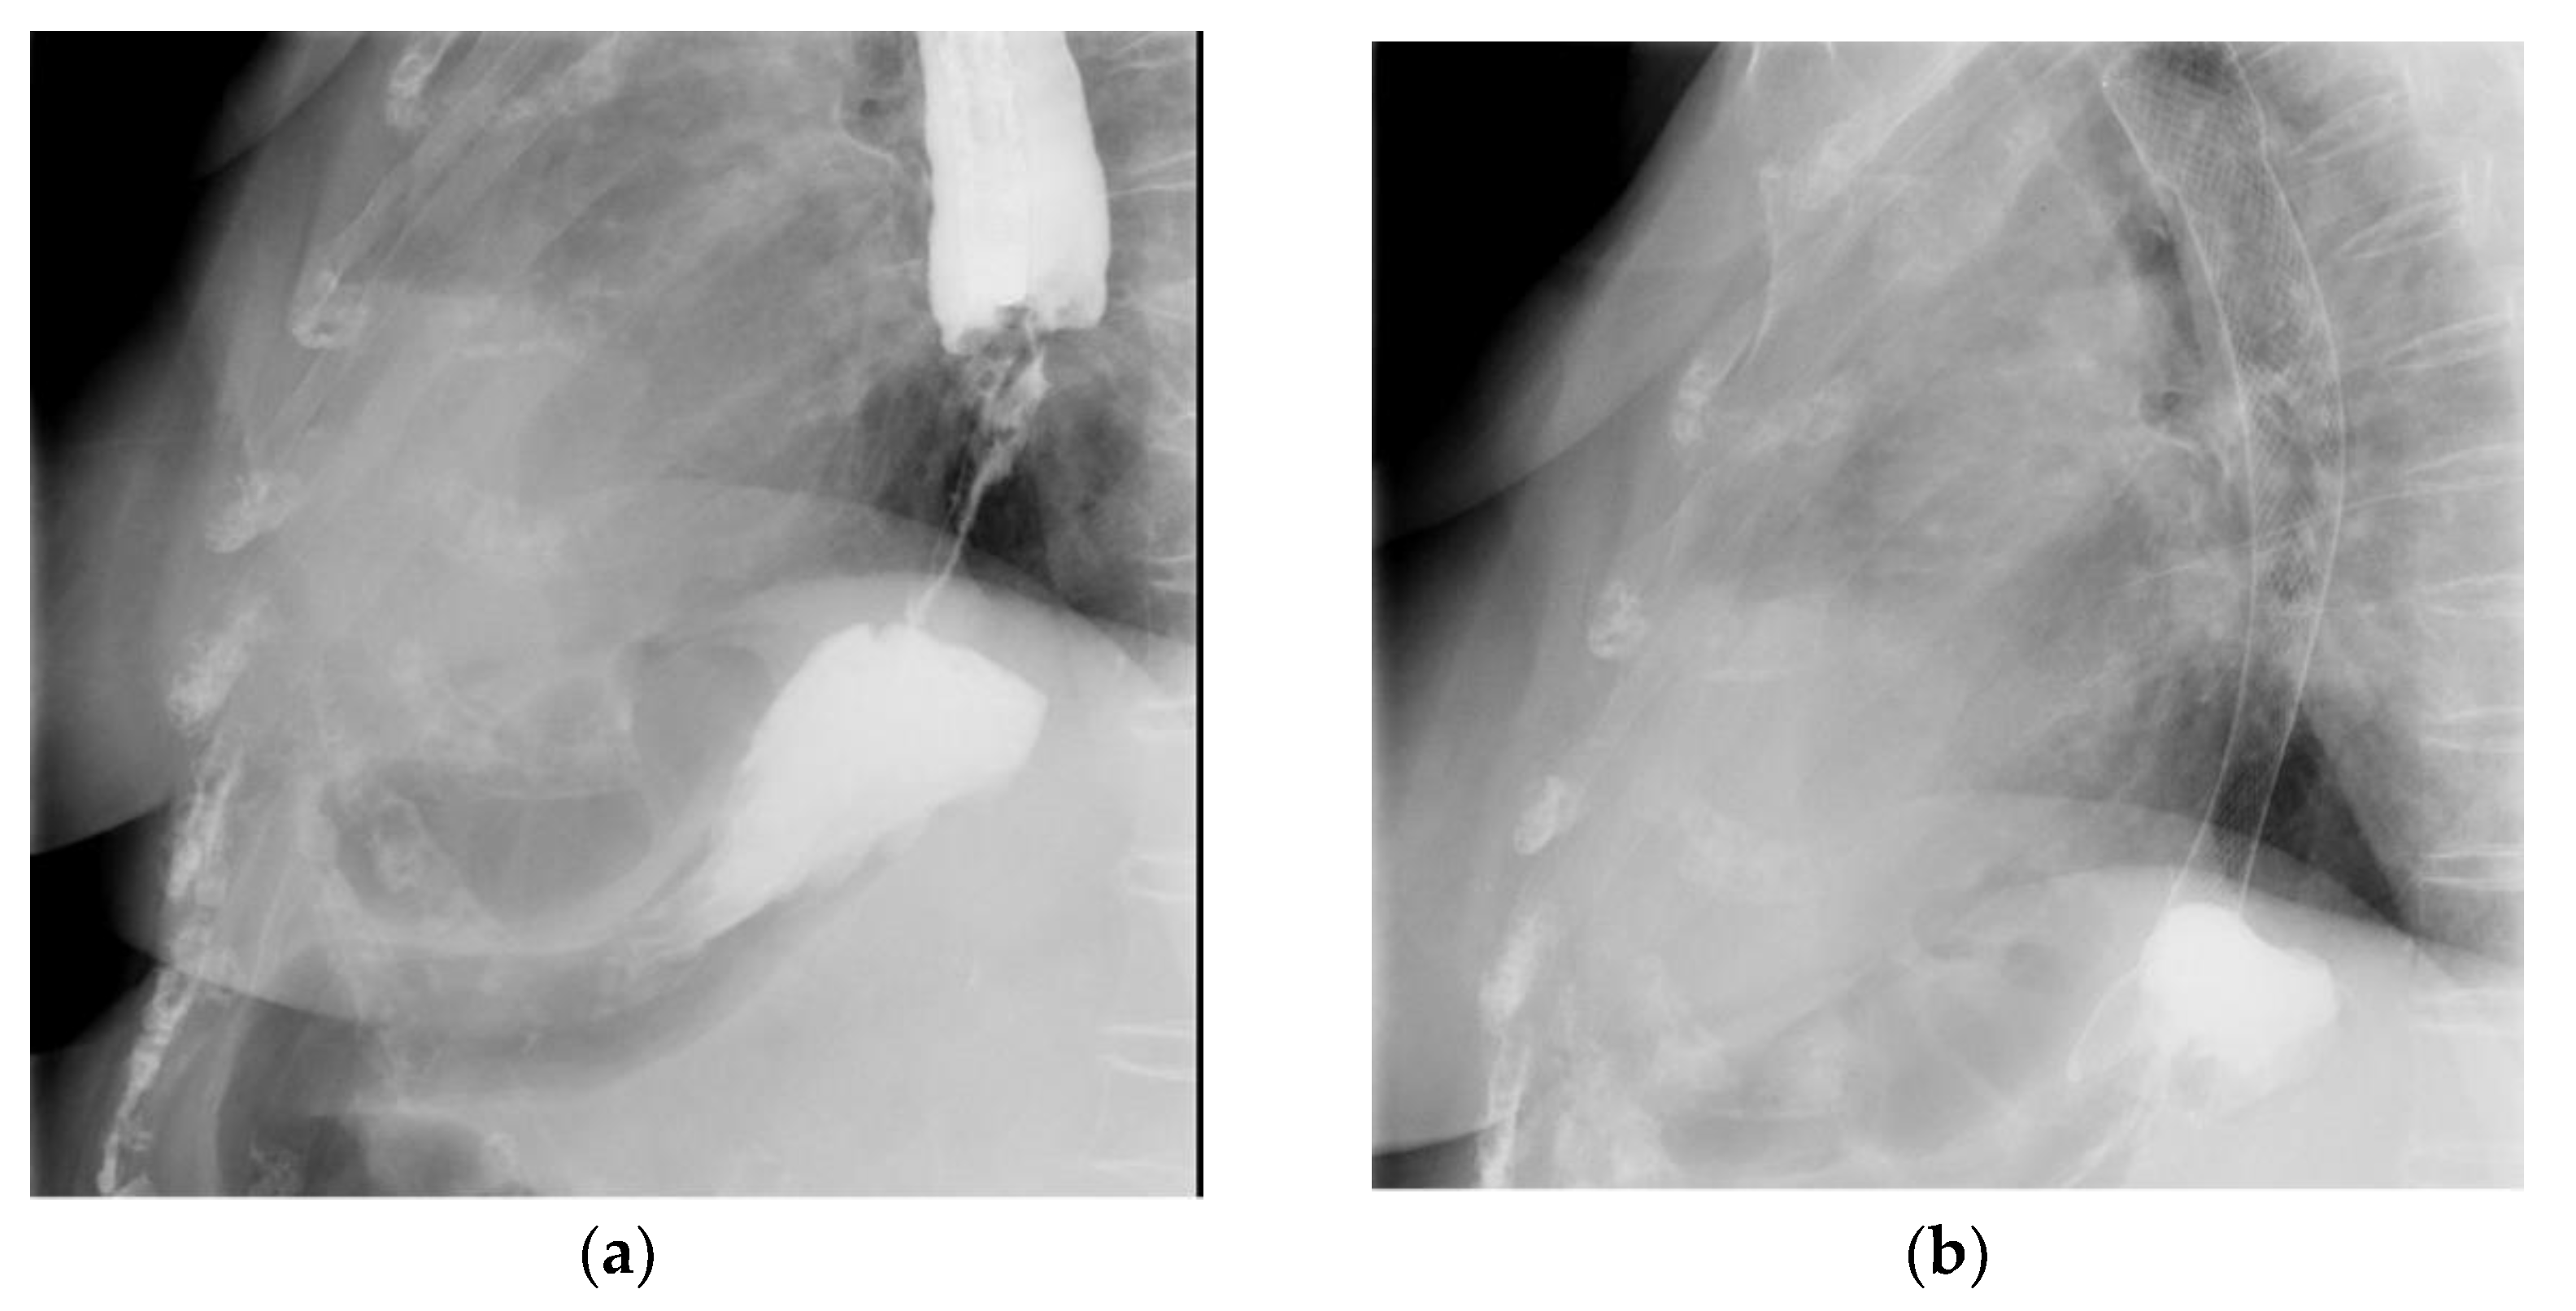

2.4. Non-Endoscopic Methods for Gastrostomy/Jejunostomy